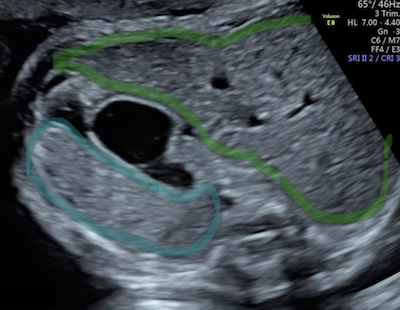

Guida al Counselling di Ottobre 2025: epatosplenomegalia

vi presentiamo la guida al counseling di Ottobre 2025 sull’epatosplenomegalia